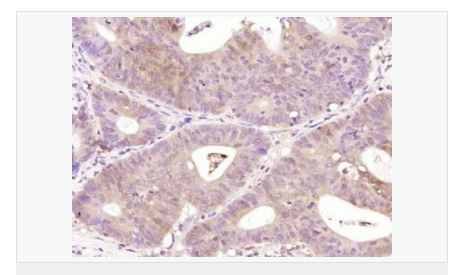

產品應用WB=1:500-2000 ELISA=1:5000-10000 IHC-P=1:100-500 IHC-F=1:100-500 (石蠟切片需做抗原修復)

產品介紹The Bcl-2 gene was isolated at the chromosomal breakpoint of t(14;18)-bearing follicular B cell lymphomas(1,2).Bcl-2 blocks cell death following a variety of stimuli and confers a death-sparing effect to certain hematopoietic cell lines following growth factor withdrawal (3,5).Bcl-2 appears to function in several subcellular locations yet lacks any known motifs that would confer insight into its mechanism of action (6,7).A more recently identified protein,designated Bax p21(i.e., Bcl-associated X protein ),has extensive amino acid homology with Bcl-2 and both homodimerizes and forms heterodimers with Bcl-2(8). Overexpression of Bax accelerates apoptotic death induced by cytokine deprivation in an IL-3 dependent cell line and Bax also counters the death repressor activty of Bcl-2(8).